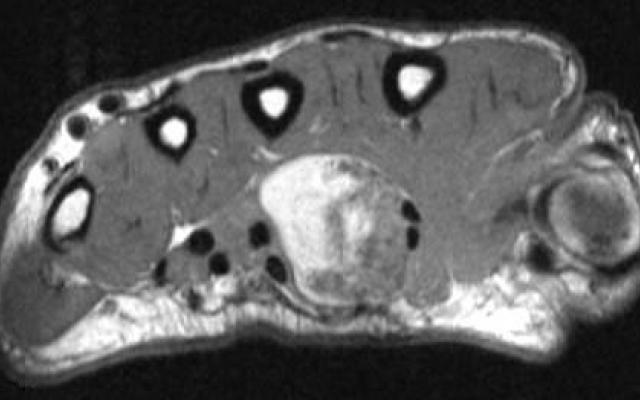

Een 41-jarige man bezocht de polikliniek Chirurgie met een sinds jaren bestaande, langzaam groeiende zwelling aan de volaire zijde van zijn linker hand. Bij lichamelijk onderzoek vonden wij een vast-elastische, niet-mobiele zwelling met een doorsnede van 2 cm. Een röntgenfoto, een echo en een MRI-scan van de hand toonden een inhomogene tumor met grove calcificaties (figuren 1 en 2). Deze tumor bevond zich in de carpale tunnel en breidde zich naar distaal uit; de N. medianus werd gecomprimeerd. Vanwege de verdenking op een liposarcoom werd patiënt doorverwezen naar een tertiair centrum. Een histologisch biopt toonde echter geen aanwijzingen voor…